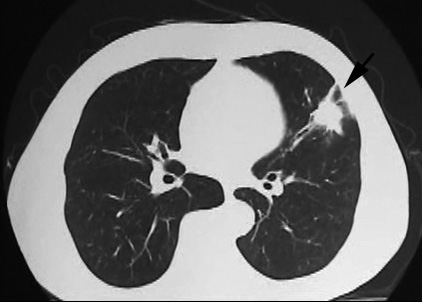

• X線検査では,通常,両肺の中・下部領域に多数の空洞化した転移性結節が認められる. 肺外への浸潤は極めて稀. 皮膚,中枢神経系,肝臓,腎臓などにも転移が見られる.

5年前から胸部CTで両肺底部にすりガラス影が出現, 間質性肺炎を指摘された. 2年前に治療強化のためエタネルセプト(TNF-α阻害薬. 商品名エンブレル)が導入された(T-spot test陰性確認後).

今月定期受診で1年ぶりにchest X-pを撮影. 両肺野に多発結節影が指摘されて受診となった.

File not found: chestXP-LYG_s.jpg File not found: LYG-CT01_s.jpg chestX-pとCT.サムネイル画像クリックで大きな画像がみられます.